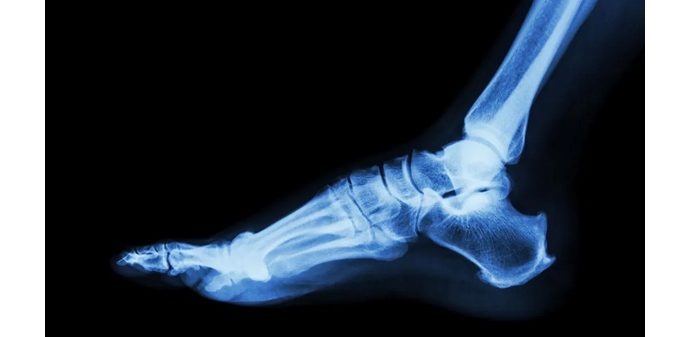

The Gorilla Pilon Fusion Plating System offers a solution for primary tibiotalar fusion in patients with pilon fractures. Pilon fractures account for approximately 7% to 10% of all tibial fractureswith a small but clinically significant group of patients requiring primary ankle fusion due to severe comminution or articular surface loss.1

Developed in collaboration with leading orthopedic trauma foot and ankle surgeons, the system delivers reliable dual-column fixation for severe or malunited tibial pilon fractures. Its anatomically-contoured plates, precision-engineered instrumentation, and streamlined workflow enable stable fixation and fusion in a single procedure. Dual-plating constructs — available in various lengths — feature contoured anterolateral and medial options, optimized for both open and percutaneous approaches. Type II anodized plates are biomechanically engineered with region-specific thickness and tapered ends to reduce soft tissue disruption. Additional features include advanced percutaneous guides, long-shaft plate designs to span metaphyseal comminution and comprehensive joint preparation instrumentation.

“This is only the second plate on the market specifically designed for primary ankle fusion in the setting of comminuted pilon fractures,” said Dr. Clayton Bettin, Division Chief of Hospital Orthopedics at Campbell Clinic in Memphis, Tenn. “The Gorilla Pilon Fusion System offers a lower-profile option that is anatomically contoured and enables stable fixation across both columns. It’s a major step forward in treating these otherwise devastating injuries.”